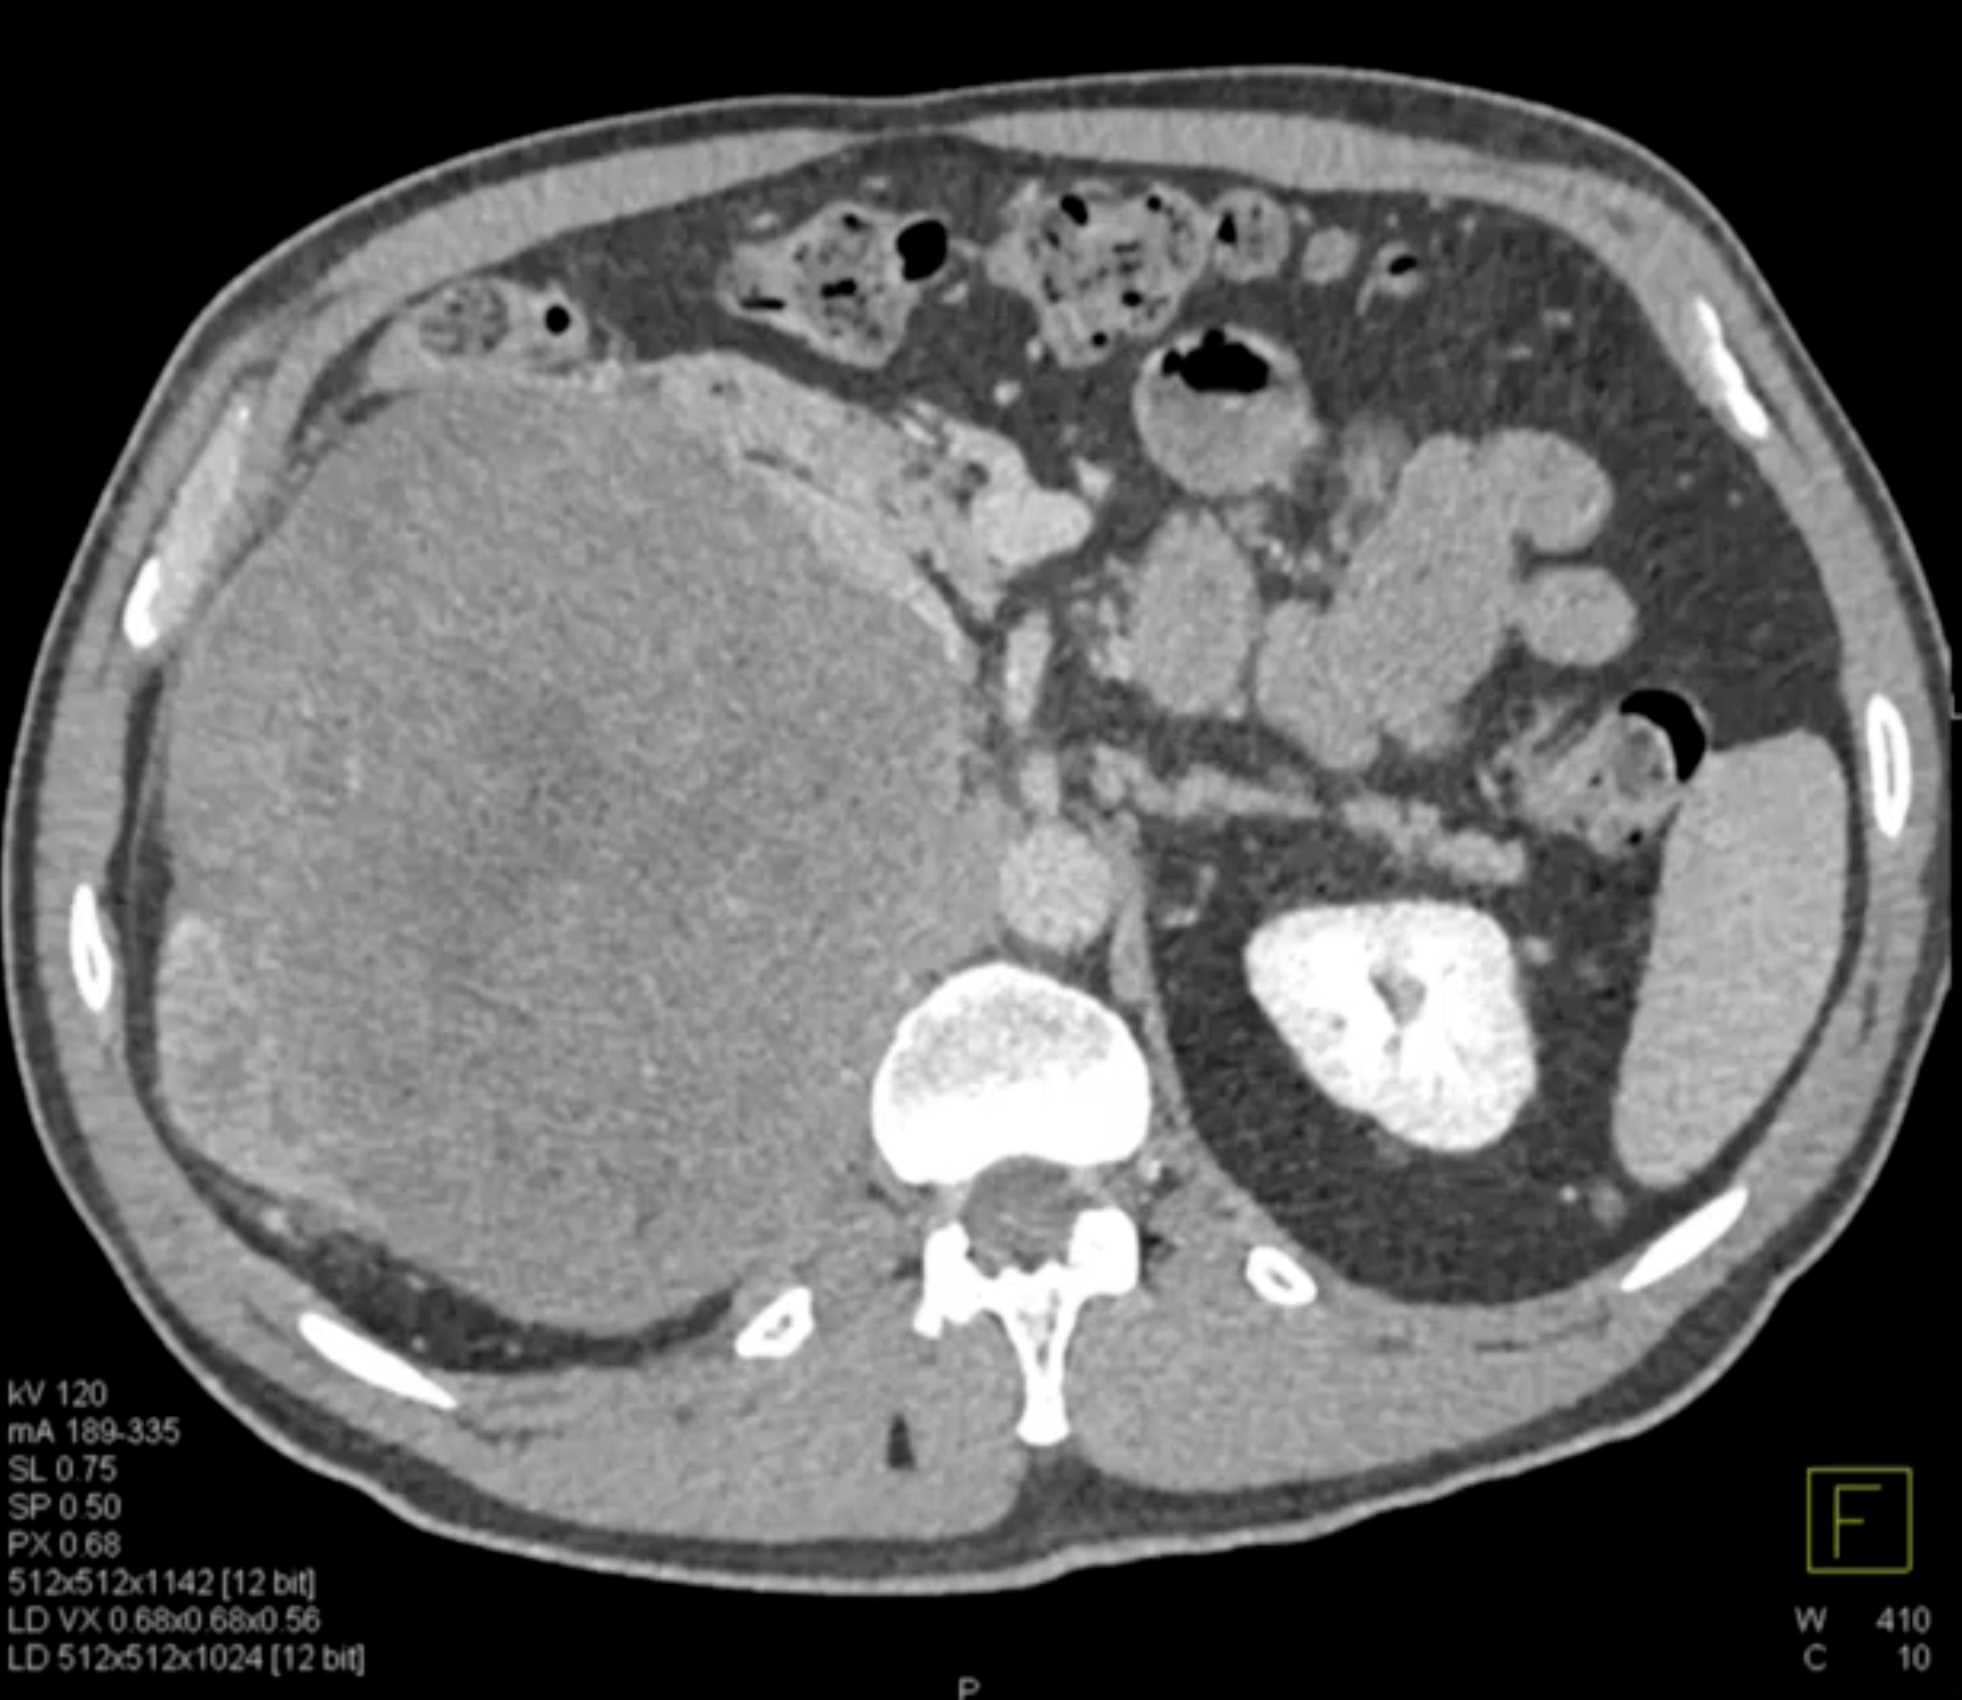

Left Adrenal Metastases from Renal Cell Carcinoma